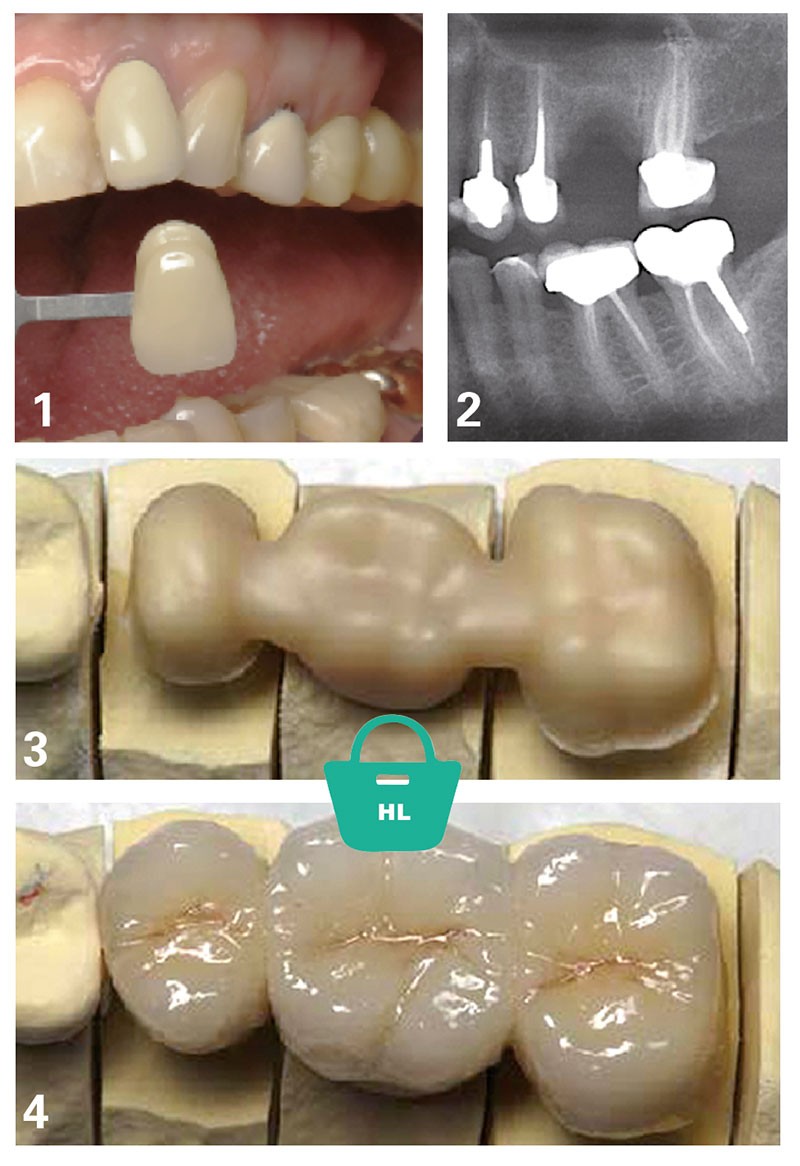

Dans le cas exposé figures 1 à 4, le traitement prothétique proposé pour remplacer la 26 peut être la couronne sur implant (avec sinus-lift) ou le bridge traditionnel 25-[26]-27.

La patiente écarte d’emblée le sinus-lift et préfère le bridge traditionnel, les futurs piliers ayant déjà des coiffes prothétiques.

Quel bridge lui proposer alors ?

La situation clinique apporte souvent une réponse claire. Ici, il paraît indispensable de proposer une solution esthétiquement acceptable, comparable aux coiffes céramo-métalliques déjà présentes sur les dents piliers. On peut, bien sûr, à partir du 1er janvier 2020, évoquer une solution RAC-0 dans pareille situation, c’est-à-dire un bridge métallique ! Mais le contexte clinique s’impose et s’oppose à une telle alternative.

Ainsi, en pratique (tableau 1) :

– jusqu’au 1er janvier 2020, les honoraires du traitement prothétique par bridge sont fixés librement, avec tact et mesure, au moyen d’un devis préalablement établi ;

– au 1er janvier 2020, on peut évoquer le bridge métallique RAC-0 à titre d’information, mais cette solution n’est pas envisageable dans ce contexte clinique ;

– au 1er janvier 2021, le bridge céramo-métallique pour remplacer une dent autre qu’une incisive entre dans le panier RAC-M. Le bridge céramo-céramique reste dans le panier HL.